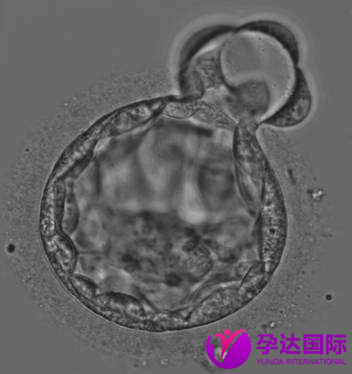

2017年11月30日,我终于等到了移植的那天。那一幕一直印象深刻。当时老公可以陪着我进去,这点挺人性化。在一个屏幕上,我们看到一个小白点。医生轻声说,那个白点就是囊胚,这就给你放进去了啊。那个感觉好神奇,好像就是看见了自己的孩子似的。

我们请求拍了照片,我说要好好保存,这就是孩子的第一张照片。>>世界第一位试管婴儿怎么样了?点击了解

移植前的囊胚图片,我珍存起来。